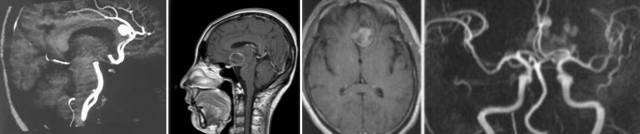

CTA—囊状动脉瘤表现为起自动脉的囊袋状突起,有蒂(瘤颈)与载瘤动脉相连,轮廓清晰;梭形动脉瘤表现为血管不规则迂曲扩张,无瘤颈。

MRI平扫:动脉瘤瘤腔内的血流呈“涡流”现象,在MRI上表现为无信号或低信号,但若动脉瘤腔内部分形成血栓,则信号改变就变得复杂化了。血栓中的正铁血红蛋白表现为高信号,若含有含铁血黄素则表现无或低信号;残留的瘤腔仍有流空效应,表现无或低信号;动脉瘤周边可有出血和水肿。

MRA:可以直接显示动脉瘤。

DSA是诊断颅内动脉瘤最准确的方法,可清晰显示动脉瘤部位、大小、数量、形状。为了发现预料之外的动脉瘤,血管造影应包括所有部位的脑内血管。